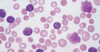

Smudge Cells

in [CLL-SLL]

[small lymphocytes w/scant cytoplasm]